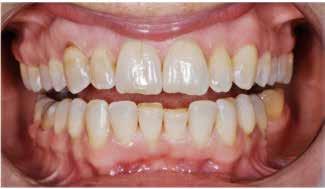

Den kliniske undersøgelse viser harmoniske ekstraorale sagittale forhold med skeletalt dybt bid (Fig. 1A, D). Hendes smil er alderssvarende med en eksponering på 8/10 af overkæbeincisiverne, mens smilets bredde er smalt med synlige mørke laterale rum (Fig. 1D). Underkæbeincisiverne er synlige under tale. Der ses neutrale okklusale forhold ved hjørnetænderne og neutrale pladsforhold i overkæben, men udtalt trangstilling i underkæben især lokaliseret i regio 1-1 (Fig. 1C).

Sliddet klassificeres som grad 2 (moderat tandslid) på de centrale incisiver i overkæbe og underkæbe. Det kan anses som patologisk, da det er atypisk for patientens alder, giver anledning til smerte/ubehag, og giver patienten et æstetisk problem. Der ses infraktioner af overkæbeincisiverne. Der ses endvidere en udtalt Spee-kurve i underkæben og ingen interincisal afstøtning på 2-2 med let ganepåbidning.

Fig. 5. A, B. Smil og kæbeforhold før og efter. Et bredere smil med korrektion af de laterale mørke rum. C-F. Harmonisk hældning af overkæbe- og underkæbeincisiver, rekonstruktion af den tabte tandsubstans efter nivellering af gingivaniveau og optimal bukko-lingval placering til direkte plastbehandling.

5. A, B. Smile and jaw relationships before and after. A wider smile with correction of the lateral dark spaces. C-F. Harmonious inclination of the upper and lower jaw incisors, reconstruction of the lost tooth substance after leveling the gingival level, and optimal bucco-lingual positioning for direct plastic treatment.